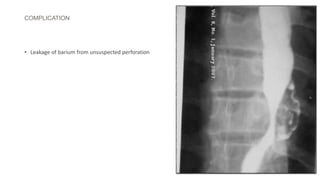

COMPLICATION

• Leakage of barium from unsuspected perforation

COMPLICATION • Leakage ofbarium from unsuspected perforation